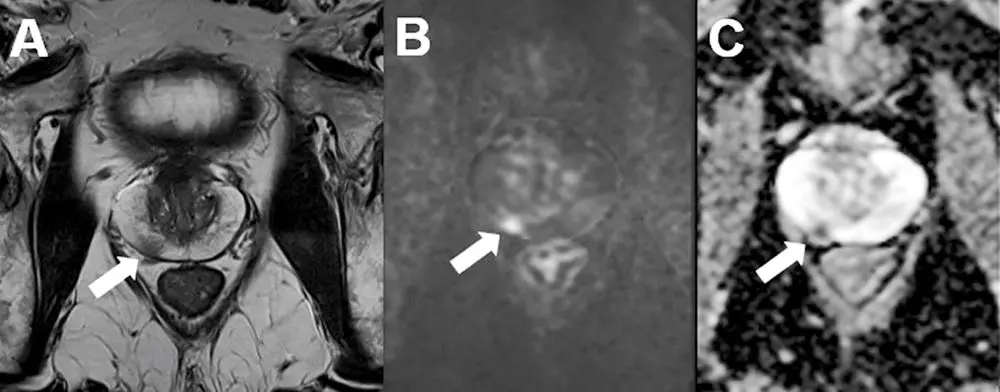

Axiale Schichtung einer mpMRT mit karzinomsuspektem Befund in der peripheren Zone rechts (PIRADS 4) in der T2-Sequenz (A) mit Nachweis einer Diffusionsstörung (B+C). Die daraufhin durchgeführte MRT-TRUS-Fusionsbiopsie der Prostata ergab ein Prostatakarzinom mit einem Gleason-Score 3 + 4 = 7a (Gleason 4-Anteil: 10 %). (mit freundlicher Genehmigung von Dr. med. Daniel Vogele, Klinik für Diagnostische und Interventionelle Radiologie, Universitätsklinikum Ulm)